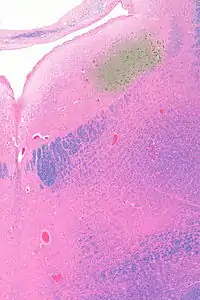

![]() Micrograph showing the locus coeruleus. HE-LFB stain. | |